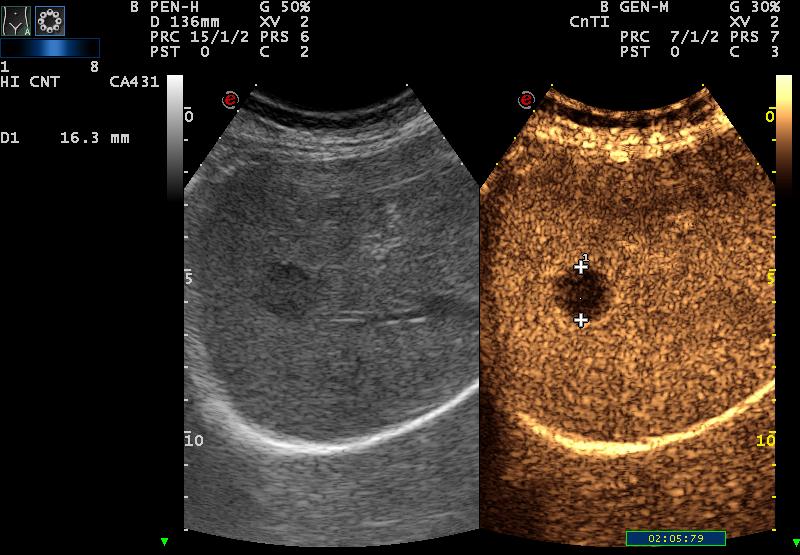

| CEUS ’29 (arterial): fast wash in |

| CEUS over 2 min: total wash out |